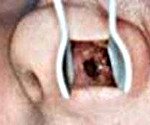

• Передняя риноскопия. Отоларинголог определяет наличие перфоративного отверстия, чаще всего - в переднем отделе носовой перегородки, которое соединяет правый и левый носовые ходы. Окружающие ткани зачастую отечны и гиперемированы. По краям отверстия присутствует большое количество сухих корочек.